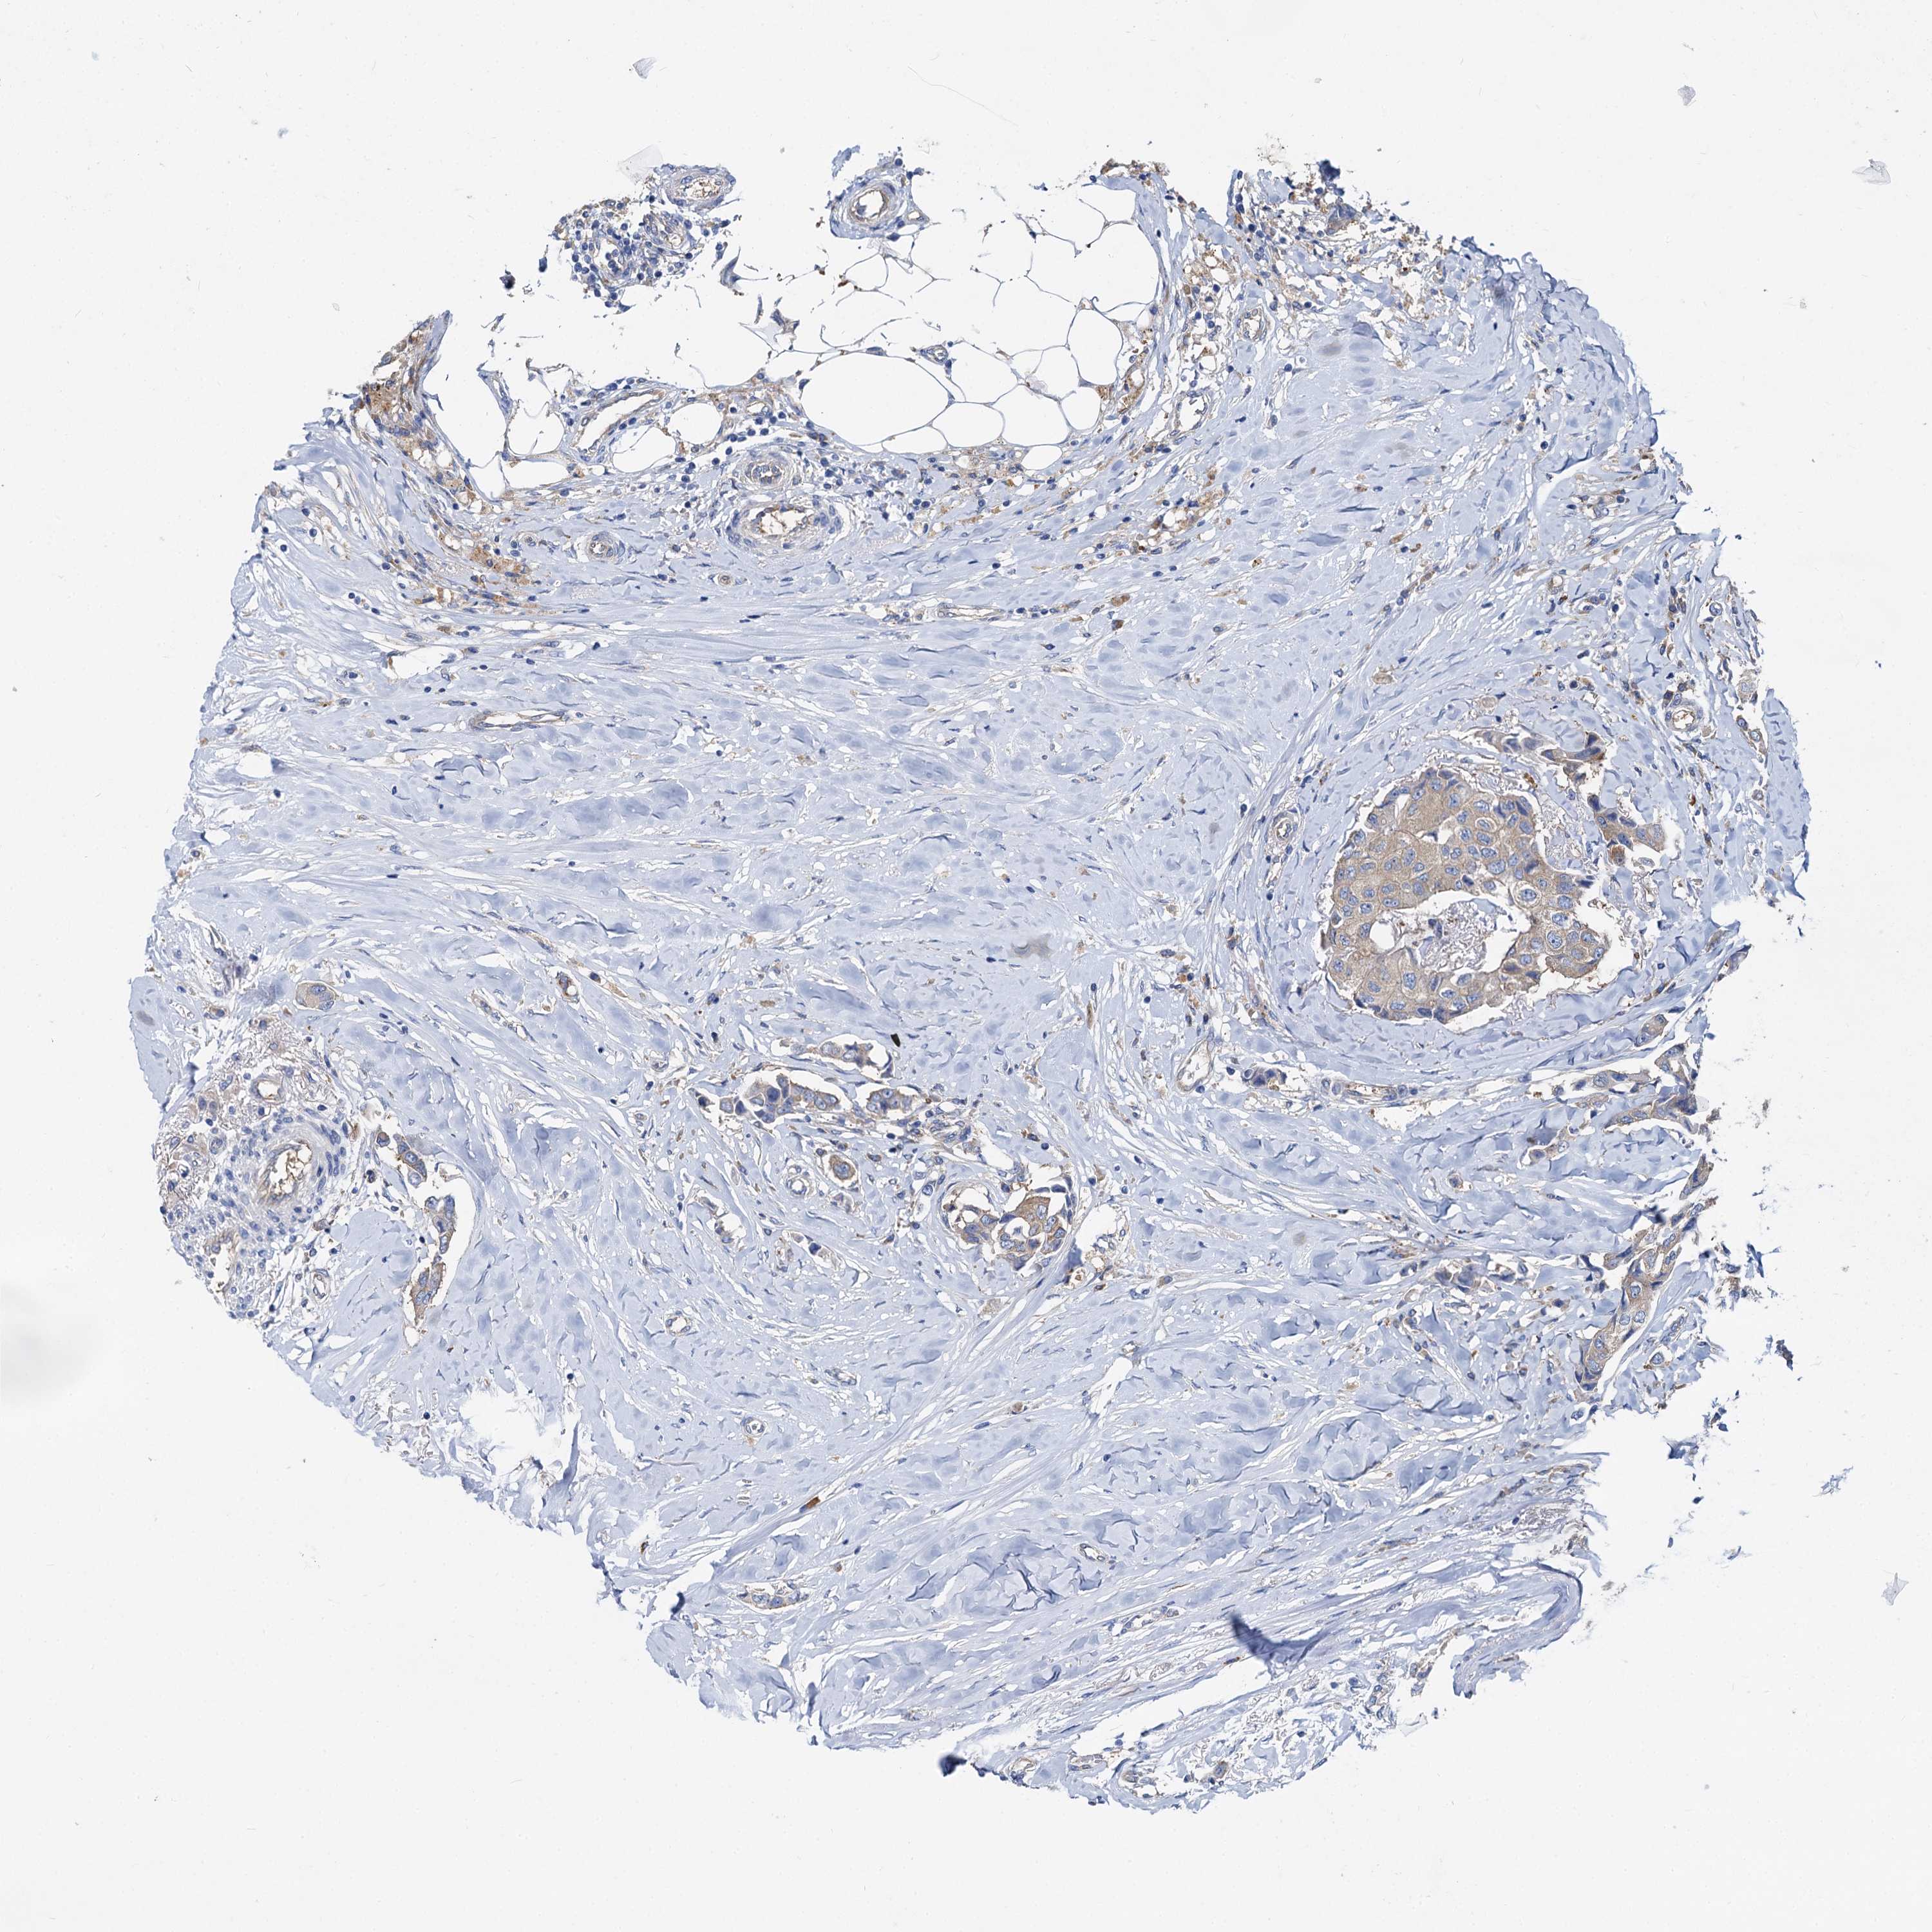

CANCER BREAST CANCER Show tissue menu

BRCA TCGA BRCA VALIDATION PROTEIN EXPRESSION